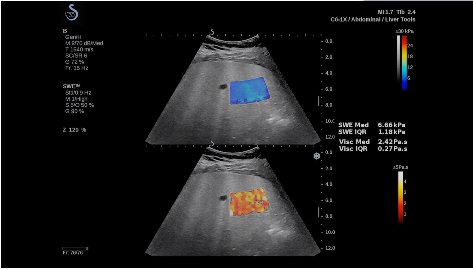

法國聲科影像(SuperSonic Imagine,SSI. Euroniex:FR0010526814)近日發(fā)表公告,宣布其研發(fā)的新一代“極速”超聲成像平臺(UltraFast Imaging),首次實現(xiàn)了肝臟的多項超聲定量評估新指標同步檢測,包括:Att PLUS,SSp PLUS和Vi PLUS等,基本涵蓋肝臟相關病理變化指征的如纖維化、脂肪變、炎癥等。據(jù)悉,此多項新技術新將搭載于新Aixplorer系列E超系統(tǒng)。

E超相關技術已被多項多中心大樣本研究證實對于肝纖維化無創(chuàng)評估有重要意義,同時也可全面應用于乳腺、甲狀腺、肝臟、前列腺、肌骨、婦科等全身各組織器官的定量評估和鑒別診斷。在慢性肝臟方面,聲科E超的肝臟相關定量診斷技術集,于2018年獲得美國FDA認證,成為FDA歷史上首次獲批的單病種超聲全面定量解決方案。

E超是在原有B超、彩超(彩色多普勒CDFI)基礎上研發(fā)成功的新一代超聲剪切波彈性成像系統(tǒng),是一種能夠全面應用于表淺組織、腹部臟器,血管等方面的組織彈性成像技術。根據(jù)組織硬度彈性值的不同,有效鑒別實性腫瘤的良惡性。對于惡性病變的診斷具有較高的特異性和敏感性,尤其對于甲狀腺、乳腺、前列腺等小器官,能夠完成常規(guī)超聲不能完成的組織定量分析,可以實時、全幅、全定量獲得組織彈性(硬度)信息,為鑒別腫瘤的良惡性提供客觀、量化的診斷依據(jù)。